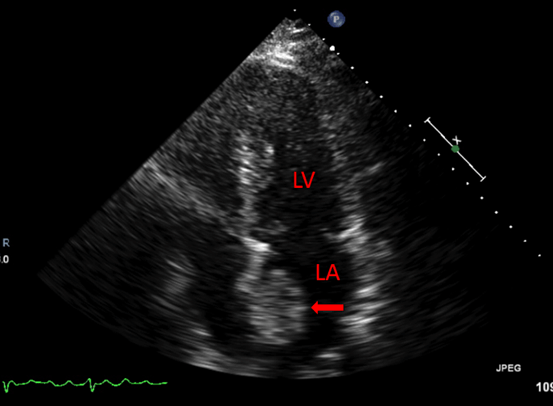

Rate control was achieved with diltiazem infusion and anticoagulation with intravenous heparin was initiated. Echocardiogram showed a left atrial mass adjacent to the interatrial septum suspicious for atrial myxoma (Figure 1). Computed tomography scan showed a left atrial filling defect that enhanced with contrast and measured 4.5x3.3x4.4 cm (Figure 2) as well as a filling defect in the superior mesenteric artery (Figure 3). Lower extremity angiogram demonstrated abrupt cessation of flow consistent with an embolus to the right popliteal artery (Figure 4) and a patent left popliteal artery. Right popliteal arterial thrombectomy was performed. The patient then underwent excision of the left atrial mass. Maze procedure and left atrial appendage ligation. The examination of excised mass revealed an organized thrombus (Figure 5). The postoperative course was uneventful and the patient was discharged on warfarin and metoprolol.

Figure 1: Echocardiogram demonstrating left atrial mass (arrow).

Abbreviations: LA Left Atrium, LV Left Ventricle.